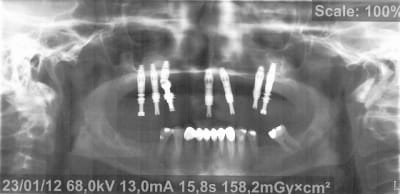

Voici donc les panos pour vos petits yeux ébahis

Profitez bien : elles sont ds l ordre chronologique...

(On est loin de tout comprendre sur les panos un peu floue, si ce n'est qu'à la fin totu est perdu)

- On y voit un manque flagrant de densité du greffon

- On y voit une perte d'un implant sans changement de plan de traitement, on se retrouve avec un seul implant du coté où mastique le patient

- On y voit une armature qui baille sur le seul implant qui reste secteur 2, et donc manque de passivité

- On y voit ce qui devait arriver,

Mais je vois aucun rapport entre l’échec et la nature du matériau mis en place dans le sinus....